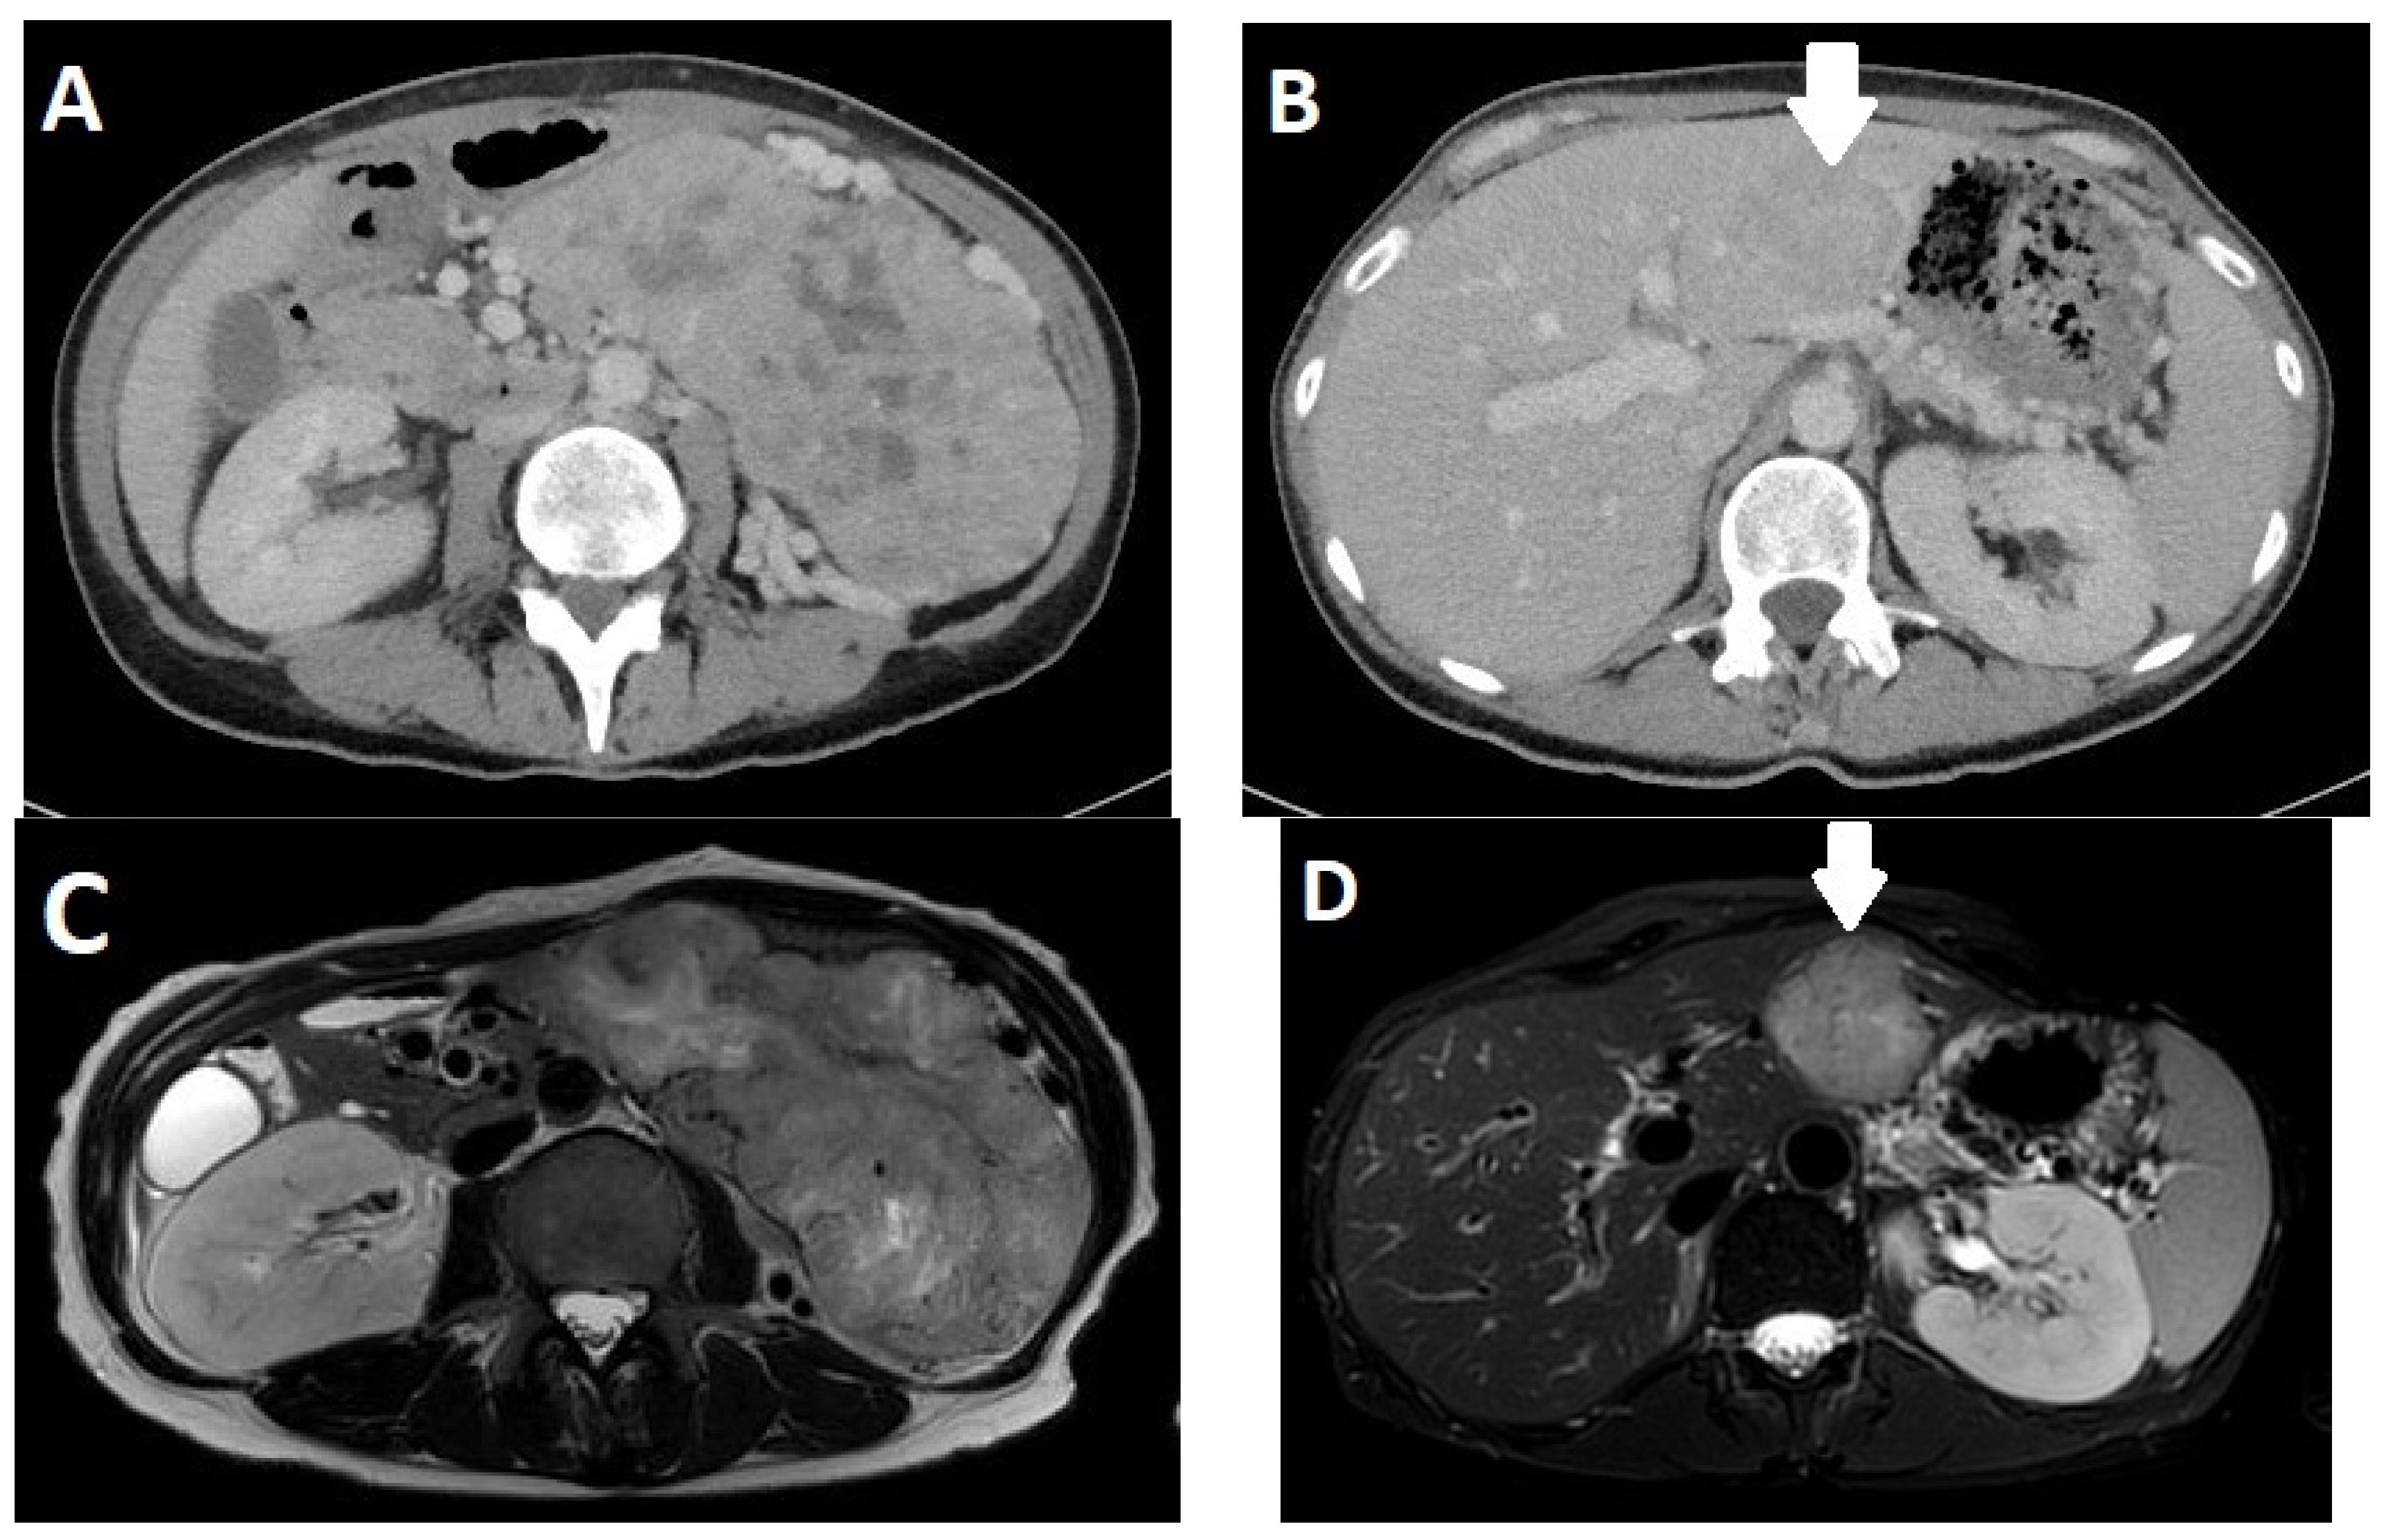

3.4. Imaging

- Owen, N.J.; Sohaib, S.A.; Peppercorn, P.D.; Monson, J.P.; Grossman, A.B.; Besser, G.M.; Reznek, R.H. MRI of pancreatic neuroendocrine tumours. Br. J. Radiol. 2001, 74, 968–973. [Google Scholar] [CrossRef]

- Bicci, E.; Cozzi, D.; Ferrari, R.; Grazzini, G.; Pradella, S.; Miele, V. Pancreatic neuroendocrine tumours: Spectrum of imaging findings. Gland. Surg. 2020, 9, 2215–2224. [Google Scholar] [CrossRef]

- d’Assignies, G.; Fina, P.; Bruno, O.; Vullierme, M.P.; Tubach, F.; Paradis, V.; Sauvanet, A.; Ruszniewski, P.; Vilgrain, V. High sensitivity of diffusion-weighted MR imaging for the detection of liver metastases from neuroendocrine tumors: Comparison with T2-weighted and dynamic gadolinium-enhanced MR imaging. Radiology 2013, 268, 390–399. [Google Scholar] [CrossRef]

- Harimoto, N.; Araki, K.; Hoshino, K.; Muranushi, R.; Hagiwara, K.; Ishii, N.; Tsukagoshi, M.; Igarashi, T.; Watanabe, A.; Kubo, N.; et al. Diffusion-Weighted MRI Predicts Lymph Node Metastasis and Tumor Aggressiveness in Resectable Pancreatic Neuroendocrine Tumors. World J. Surg. 2020, 44, 4136–4141. [Google Scholar] [CrossRef]